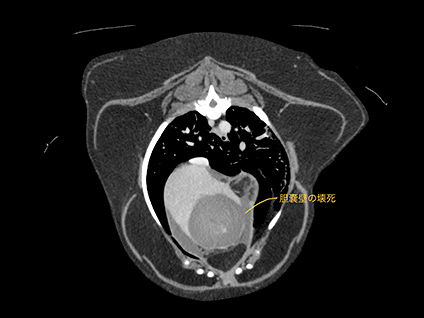

腫瘍性疾患におけるCT検査

腫瘍性疾患のCT検査は、病変の位置や浸潤、転移の有無など、手術前の検査としての役割や、抗癌剤などの治療効果判定としての役割があります。病変部やその周囲を細かく立体的にイメージできるようになるため、「より安全な手術、癌の早期発見」につなげる事ができます。